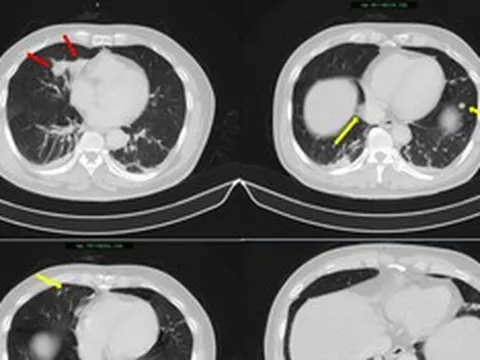

Trường hợp ông N.N.T (53 tuổi) được đưa vào bệnh viện trong tình trạng hôn mê sau khi xuất hiện mệt và đau ngực lúc đang sinh hoạt.

Người nhà bệnh nhân cho biết khoảng 15 phút trước nhập viện, ông đột ngột mệt nhiều, sau đó ngã và mất ý thức. Khi đến bệnh viện, người đàn ông này rơi vào ngừng tim. Các bác sĩ phải sốc điện 45 phút, tim mới đập trở lại.

Qua thăm khám, khai thác tiền sử bệnh các bác sĩ thấy bệnh nhân có nhiều yếu tố nguy cơ tim mạch: Hút thuốc lá 10-12 điếu mỗi ngày, rối loạn mỡ máu, thường xuyên thức khuya đến khoảng 23h và đặc biệt là sử dụng cà phê với tần suất rất cao, khoảng 10 ly/ngày.

Theo Bác sĩ Mạnh, nhồi máu cơ tim xảy ra do sự tắc nghẽn đột ngột dòng máu nuôi tim, phổ biến nhất là do mảng xơ vữa động mạch vành bị nứt vỡ, tạo cục máu đông. Nguyên nhân chính bao gồm: Tăng huyết áp, rối loạn lipid máu, hút thuốc lá, tiểu đường, lối sống ít vận động, và căng thẳng (stress) quá mức. Ở bệnh nhân trên có đủ yếu tố này.